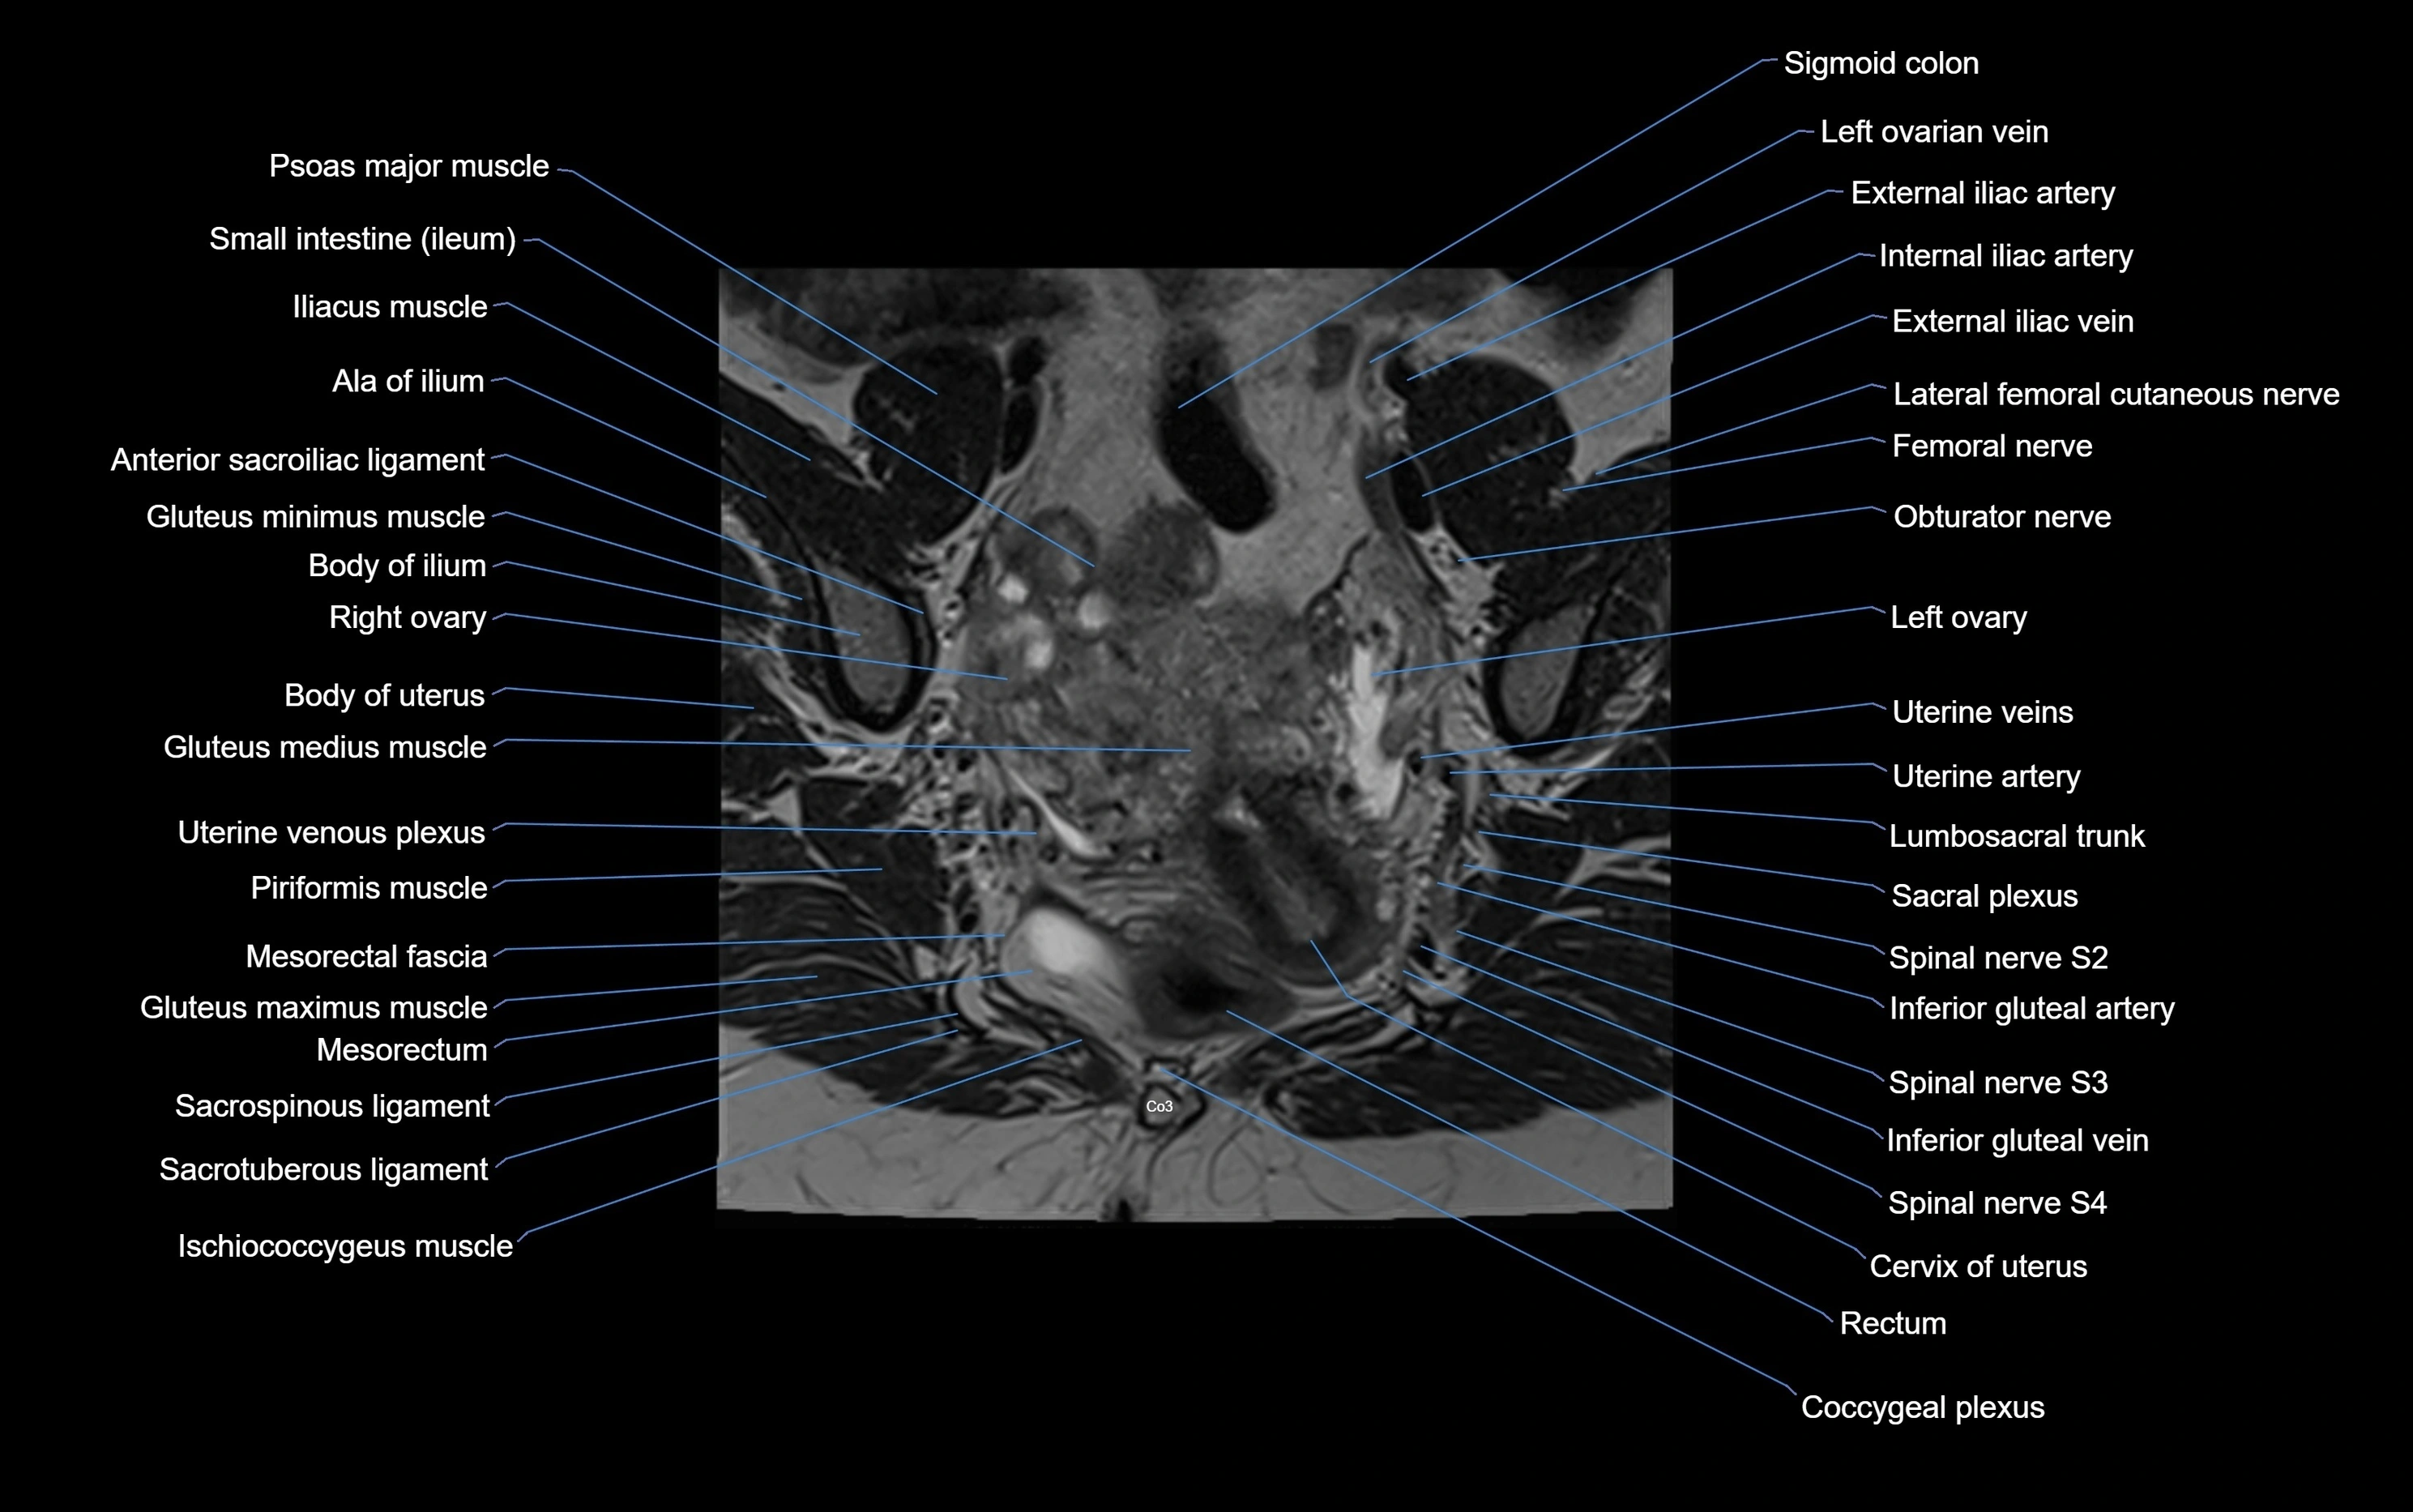

MRI Appearance

T1-weighted images:

• Cortical bone appears very low signal (dark); marrow shows intermediate signal

• Iliac fossa fat is bright against low-signal cortex

T2-weighted images:

• Cortical bone remains dark

• Marrow signal varies depending on fat content; edema or tumor shows hyperintensity

STIR:

• Suppresses fat, making bone marrow edema, fractures, or infiltrative lesions appear bright

• Excellent for trauma, sacroiliitis, and metastatic evaluation

T1 Fat-Saturated (Pre-contrast):

• Marrow: intermediate signal, fat suppressed

• Useful for detecting subtle marrow abnormalities adjacent to iliac cortex

T1 Fat-Saturated Post-Contrast (Gadolinium):

• Enhances vascularized structures, marrow pathology, tumors, and inflammatory changes

• Highlights soft tissue or bone invasion in pelvic neoplasms

MRI Non-Contrast 3D Imaging:

• Provides 3D morphology of iliac wing, crest, and articulations

• Used in preoperative planning for pelvic surgery and trauma reconstruction

MRI image

image